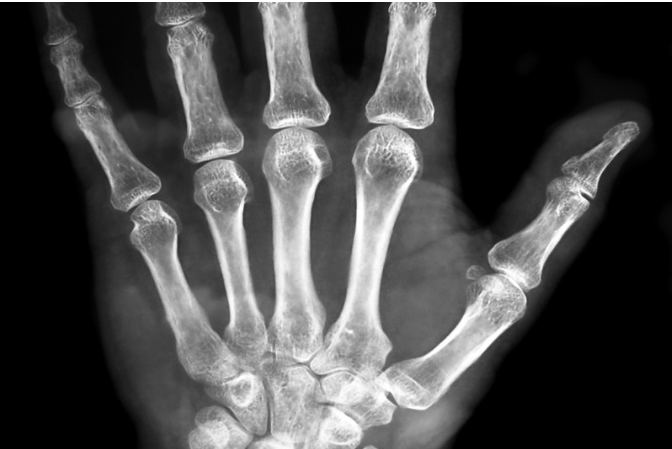

手首の真ん中に正中神経という神経が走っており、その正中神経の通り道が狭くなると、親指から人差し指、中指、薬指の一部にしびれ痛みをきたします。これを手根管症候群と言います。明け方に強くなり、手を振ることで楽になります。親指の付け根が瘦せてきて、縫物やボタンかけなどの細かな作業がやりにくくなり、図のようなOKサインができなくなります。

手根管症候群の診断

しびれ・痛みの範囲の確認と、ハンマーで手首を軽く叩くことで痛みを誘発するティネル サインの有無で手根管症候群を診断します。レントゲンで手首の変形がないかも確認し、また神経伝導検査を行い、NCVの低下や潜時延長を確認いたします。